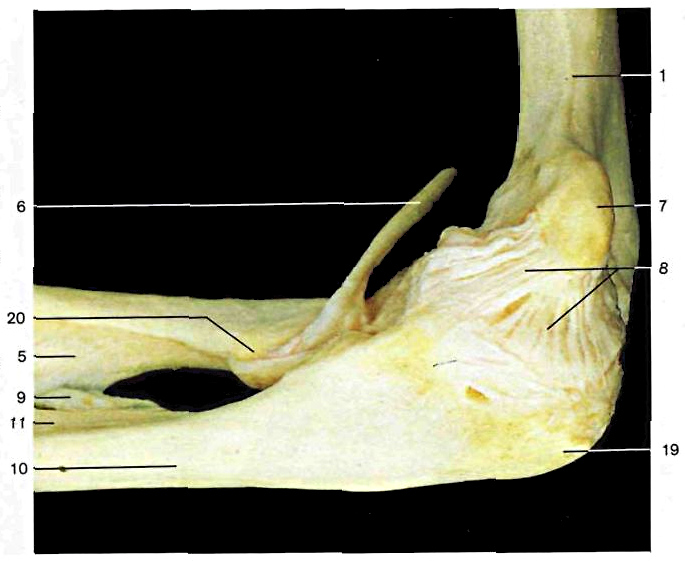

1. Omero; 2. Epicondilo omerale; 3. Capsula articolare; 4. Legamento anulare del radio; 5. Radio; 6. Tendine del muscolo bicipite; 7. Epitroclea; 8. Legamento laterale interno (collaterale ulnare); 9. Corda obliqua (legamentosa di Weilbrecht); 10. Ulna; 11. Membrana interossea dell'avambraccio; 12. Fossa condilica; 13. Condilo omerale; 14. Testa del radio; 15. Legamento laterale esterno (collaterale radiale); 16. Fossa coronoidea; 17. Troclea omerale; 18. Apofisi coronoide dell'ulna; 19. Olecrano; 20. Tuberosità bicipitale (del radío)